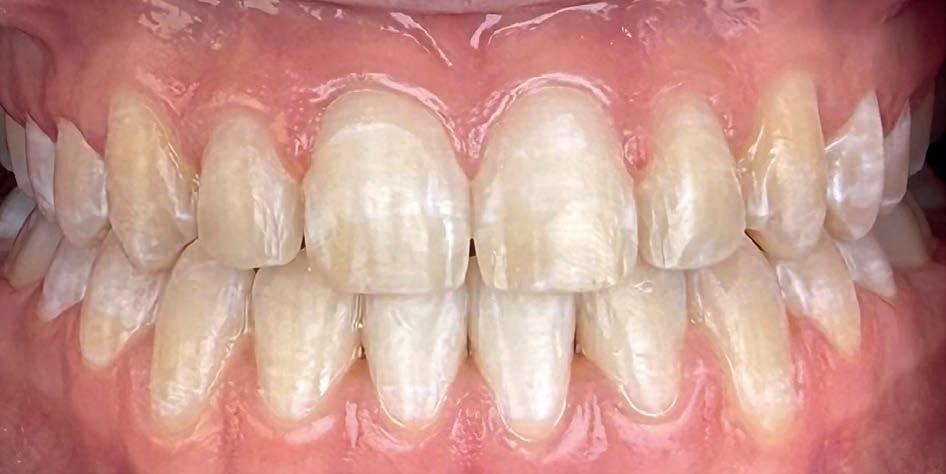

Casus in Proces

Patiënt Sonnie presenteerde zich met ernstig ruimtegebrek ter hoogte van de 13 en 44 en een kruisbeet aan de zijde van de 15 en 14. De 13 was ectostematisch gepositioneerd, waardoor extractie aanvankelijk als mogelijke behandeloptie werd overwogen.

Door een combinatie van verbreding en het inzetten van een D-gainer wordt de benodigde ruimte gecreeerd om alle elementen correct in de tandboog te positioneren, waardoor extracties kunnen worden vermeden. De behandeling zal binnen twee jaar worden afgerond; het eindresultaat wordt gedeeld in editie 2 van ons magazine.

Laatste fase